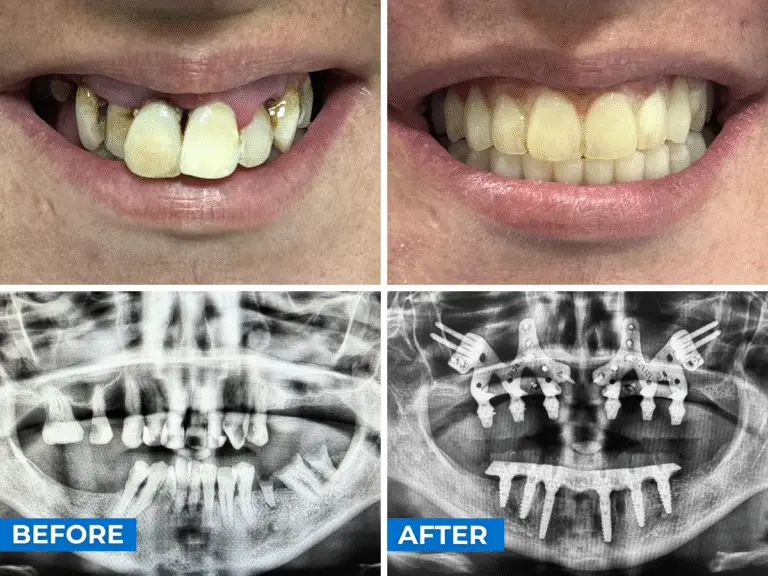

Subperiosteal Dental Implant: Before and After

These real clinical cases from Smile24h Expert Clinics, performed by certified Smile24h doctors, demonstrate how advanced, customised implant solutions can restore stability, function, and aesthetics even in cases of extreme bone loss — delivering immediate improvements in comfort, confidence, and quality of life.

A 38-year-old patient who presents with generalized bone loss, significant mobility, and infections. After performing the CT scan, They observed that there is very little bone thickness and, in addition, in the area of the zygomatic bone the bone is extremely scarce and very thin. Therefore, it was decided to place customized upper implants in order to take advantage of the little remaining bone, and to perform a lower rehabilitation with conventional implants — six implants — allowing for immediate loading in both the upper and lower arches.

In the photo, you can see the before and after with the provisional prostheses under immediate load.